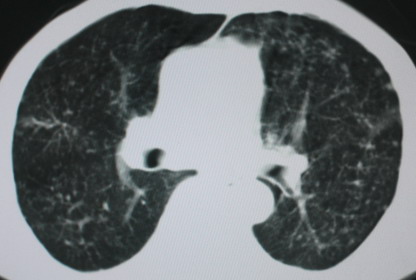

以下是引用卜一在2008-6-3 19:33:00的发言:[br]双肺结节,以双上肺分布为多,期间搀杂片状致密影及索条致密影。考虑:继发性肺结核伴血型播散可能性大。不除外肺泡ca的可能!另:椎体退变!

以下是引用panyishengct在2008-6-3 21:09:00的发言:[br]双上肺弥漫性小结节影,纵隔窗内钙化淋巴结影,考虑矽肺或/和tb可能性较大,不除外肺ca可能。腰椎考虑退变。 [br][br]